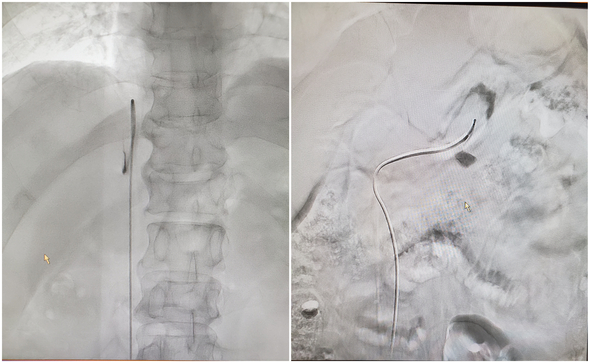

肾上腺静脉取血术中图像

介入科主任刘琳介绍,AVS实施过程中,将导管分别送至双侧肾上腺中央静脉进行采血,可以直接、准确的测定醛固酮、肾素等肾上腺局部激素水平,来判断有无优势分泌,明确患者原醛症分型,术后局部压迫止血后即可正常活动。该技术创伤小,准确性高,但肾上腺静脉血管只有二三毫米细,右侧肾上腺静脉汇入下腔静脉解剖位置及角度变化大,对于操作者的插管技术要求高,目前该项技术仅在国内少数医院开展。